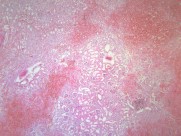

肾小管坏死(12)张

为急肾衰最常见类型,约占75%~80%.它是由于各种病因引起肾缺血及/或肾毒性损害导致肾功能急骤、进行性减退而出现的临床综合征.主要表现为肾小球滤过率明显降低所致的进行性氮质血症,以及肾小管重吸收和排泄功能低下所致的水、电解质和酸碱平衡失调.据尿量减少与否分少尿(无尿)…